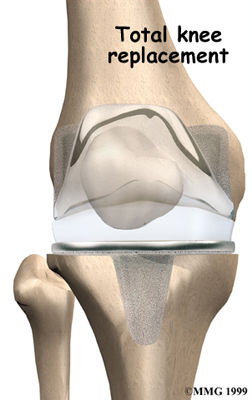

Artificial Knee Replacement

An artificial knee replacement is the ultimate solution for advanced knee OA.

Surgeons prefer not to put a new knee joint in patients younger than 60. This is because younger patients are generally more active and might put too much stress on the joint, causing it to loosen or even crack. A revision surgery to replace a damaged prosthesis is harder to do, has more possible complications, and is usually less successful than a first-time joint replacement surgery.

Related Document: FYZICAL Eastern & Tropicana's Guide to Artificial Joint Replacement of the Knee